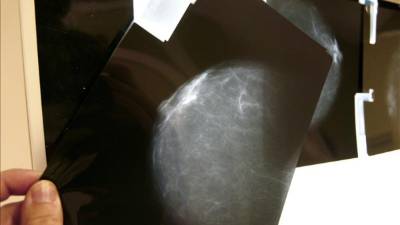

9. Mamografías obligatorias en mujeres a partir de 50 años. Estas pruebas detectan el cáncer incluso cuando aún no se han manifestado los primeros síntomas, multiplicando así la posibilidad de curación. En antecedentes familiares, los controles deben comenzar antes.